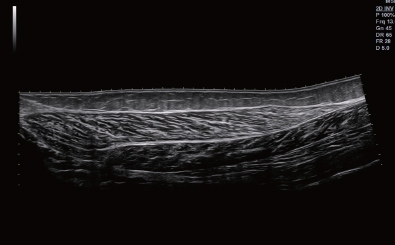

Panoramic

Silhouette